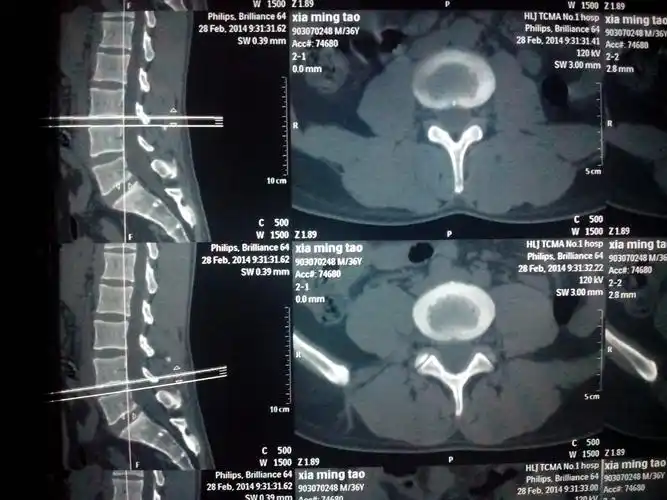

滨州市中医医院成功完成首例腰椎棘突间动态固定手术